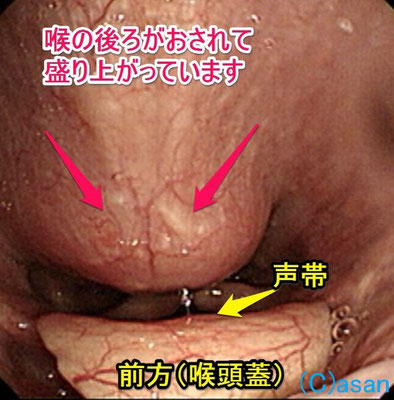

下の写真の方は飲み込む時、こする感じが続くとのことで来院されました。電子スコープで見ると喉の後方が盛り上がっています。スコープの先端で見ると硬そうです。